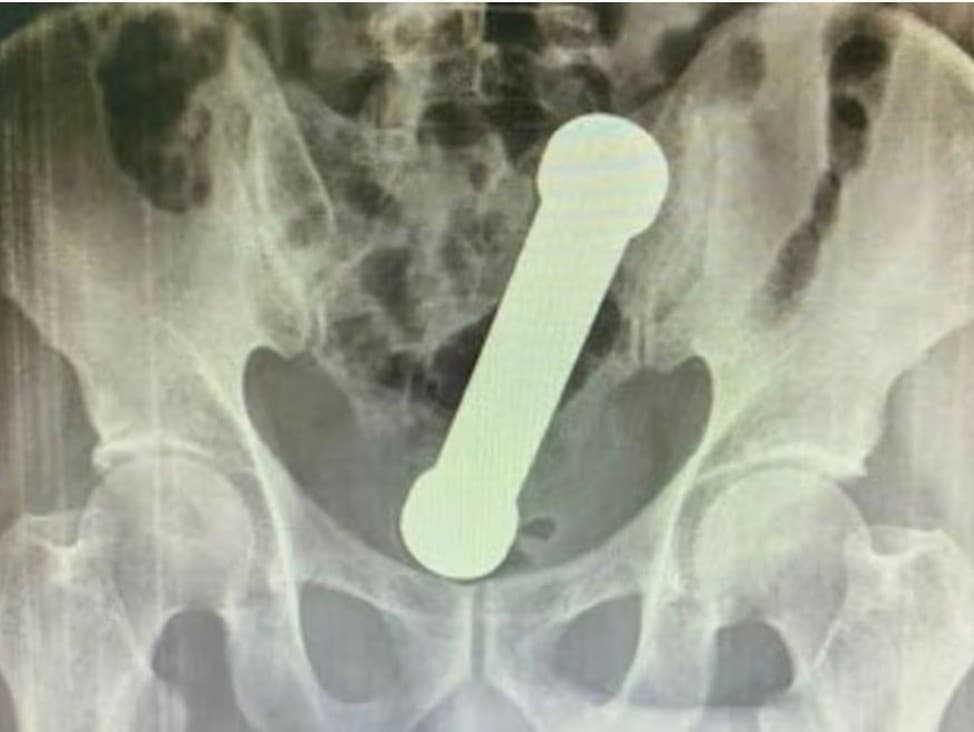

Zlom nastal až po röntgenovom vyšetrení. Lekári na snímke objavili kovovú činku dlhú približne 20 centimetrov s hmotnosťou okolo dvoch kilogramov, ktorá uviazla v oblasti konečníka a hrubého čreva.

Podľa dostupných informácií sa muž najprv pokúšal predmet odstrániť sám, no neúspešne. Až potom vyhľadal odbornú pomoc.